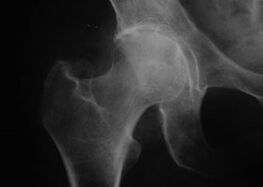

Coxatrose, Arthrose des Hüftgelenks.

Bei dieser Erkrankung wird ein klassisches Krankheitsbild der Arthrose beobachtet.

Das erste Symptom einer Coxarthrose sind Beschwerden im Hüftgelenk nach körperlicher Aktivität.

Bei fortschreitender Coxarthrose nehmen die Schmerzen zu, es kommt zu Steifheit und eingeschränkter Beweglichkeit.

Patienten mit einer schweren Form der Coxarthrose respektieren das betroffene Glied, vermeiden es, darauf zu treten und wählen im Stehen Positionen, in denen sie weniger Schmerzen verspüren.